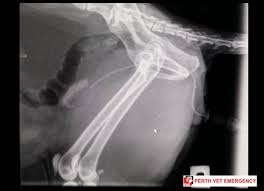

A cystotomy is a surgical opening created in the wall of the urinary bladder.

They are sometimes called renal calculi. Many cats with kidney stones have no apparent signs; Treatment is a mix of thoughtful surgery and selection of antibiotics after such surgery to kill bacteria that remain. Your physician will talk with you about the right treatment for your stones. Common kidney stone causes include: Recovery of kidney stones in cats. In cases of abnormal insertion of the ureters into the bladder (these are the thin long tubes that carry urine from the kidneys to the bladder), a cystotomy incision will be needed to correct. These stones typically need surgical intervention.

Breeds that are most affected in dogs include miniature and the exact aftercare will depend on the location of the stones and the procedure that your pet has undergone. If their kidneys aren't working properly these waste stones (calculi) and sludge can form anywhere in the urinary system from minerals in the pee. Historically, the treatment of kidney stones required major surgery and was associated with long hospitalization and recovery periods. Symptoms of bladder stones in cats. In cases of abnormal insertion of the ureters into the bladder (these are the thin long tubes that carry urine from the kidneys to the bladder), a cystotomy incision will be needed to correct.